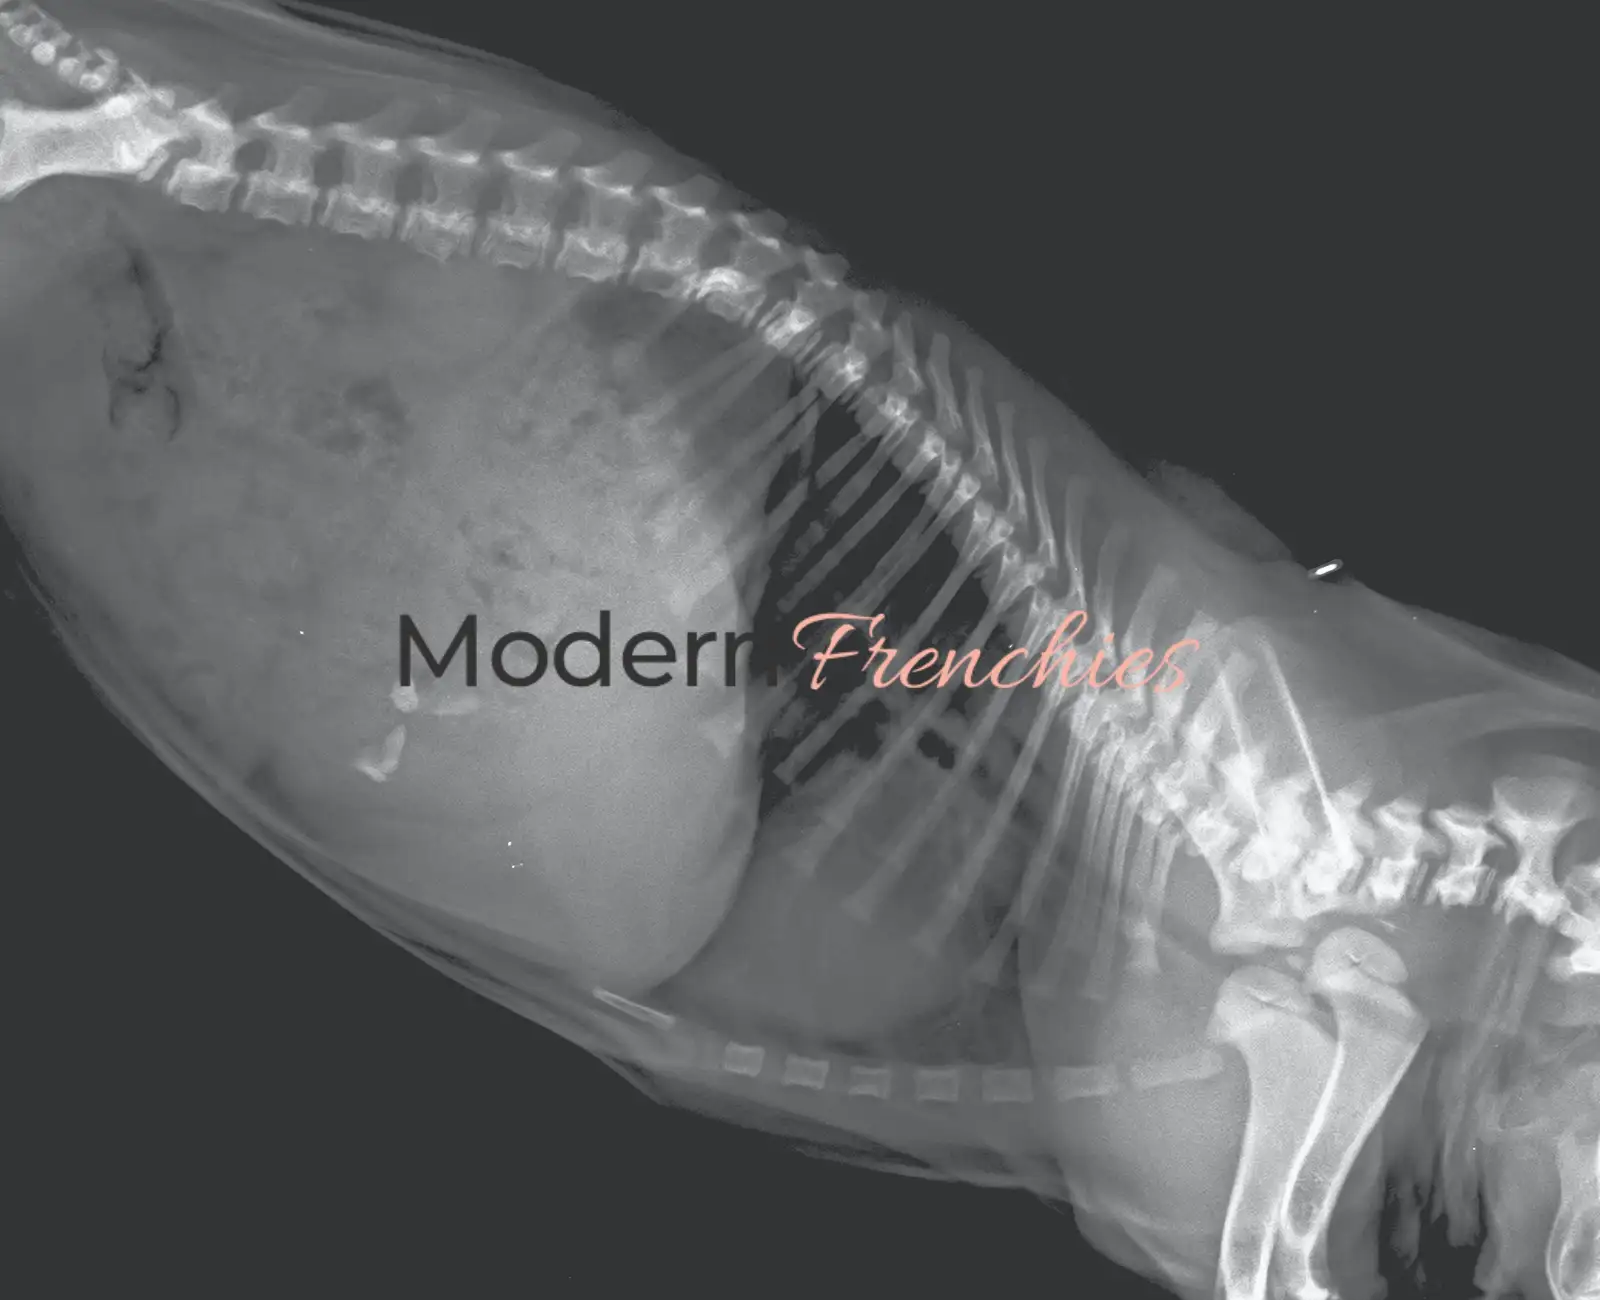

Ab der neunten Lebenswoche erfolgt der letzte tierärztliche Check mit Röntgen und Ausstellung der Gesundheitsurkunde. Jeder Welpe erhält einen individuell geplanten Abholtermin, damit der Übergang ins neue Zuhause ruhig, stressfrei und persönlich gestaltet werden kann.

•  Röntgenuntersuchung der Wirbelsäule

• Gesundheitszeugnis mit dem aktuellen Gesundheitszustand und Röntgenbild der Wirbelsäule